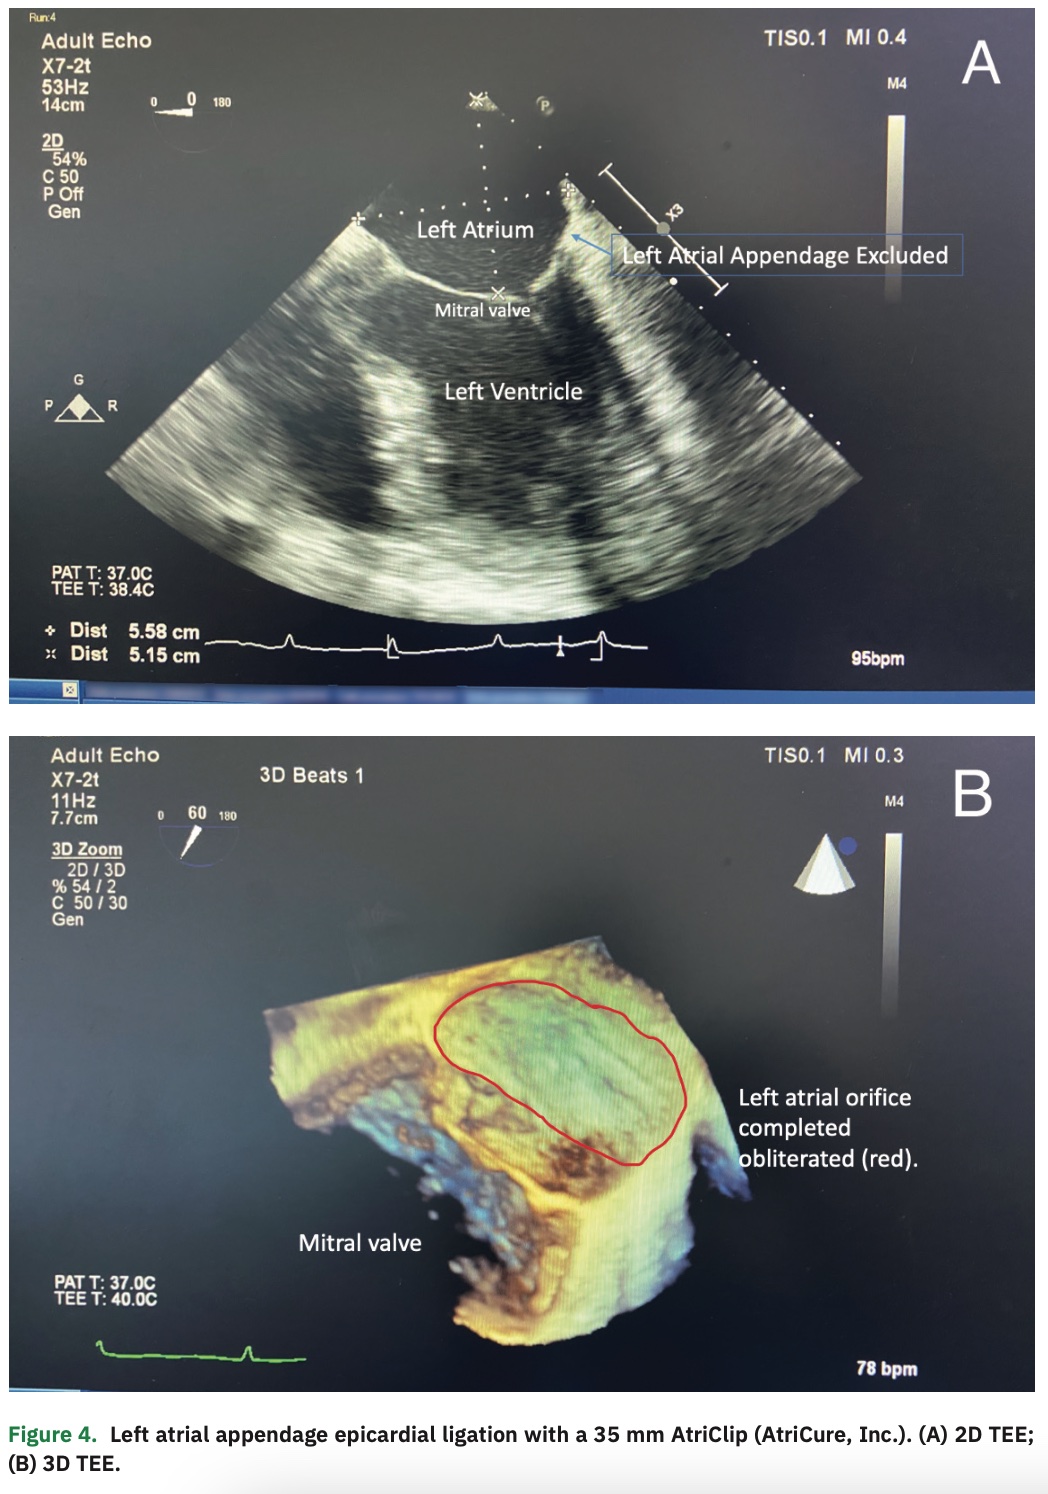

On POD #57, he returned to the EP lab with his electrophysiologist for the scheduled second stage of his hybrid ablation. His ablation was performed using standard mapping and ablation techniques. Mapping revealed well-isolated bilateral pulmonary veins with small reconnections of the roof and floor ablation lines on the right side that were successfully ablated to silence the posterior left atrial wall (Figure 3). The previously created partial mitral isthmus line was completed as well as a cavotricuspid isthmus (CTI) line, both of which confirmed bidirectional block and no recurrent atrial tachyarrhythmias with pacing and isoproterenol challenge. His LAA was found to be well occluded on transesophageal echocardiography (TEE) (Figure 4). He was discharged later that day on amiodarone and apixaban. He maintained sinus rhythm, and amiodarone and apixaban were discontinued 3 months later. The patient continues to maintain NSR 5 years later, without any symptoms of recurrence and normal annual 2-week rhythm monitors. He has significant improvement in his functional capacity, and has returned to activities such as skiing without difficulty.